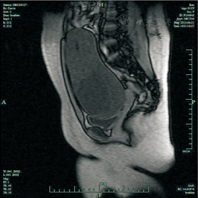

女性,13岁,因"发热、咽痛、腰痛5 d"于2013-04-19入本院。病史采集:既往史:12岁月经初潮。入院查体:T为38℃,R为18次/min,P为86次/min,体重为87 ㎏,神志清楚,精神可,全身皮肤无黄染、出血点及皮疹,手、足及肛周未见皮疹,口唇红润,口腔黏膜光滑,咽充血、无疱疹,双侧扁桃体Ⅱ°肿大、可见脓栓,呼吸平稳,颈软,双肺呼吸音清晰,未闻及啰音,HR为86次/min,心音有力,心律齐,未闻及杂音,腹软,肠鸣音正常,生理反射存在,脑膜刺激征阴性,病理反射阴性,四肢肌张力正常,双肾区无压痛及叩击痛,全身无浮肿。辅助检查:胸部X射线摄片示支气管炎;血常规示WBC计数为11.32×109/L,N为82.9%,L为12%,RBC计数为4.23×1012/L,Hb为124 g/L,PLT为293×109/L;尿常规提示尿潜血(++),蛋白质(+);肾功能及血糖正常。入院诊断为:①急性化脓性扁桃体炎,②肾炎待排,将其收入儿科。入院后给予患者抗炎及对症治疗,体温仍波动于37.7℃~39.0℃,泌尿系统超声检查提示无明显异常,盆腔超声检查示多房囊性包块(18.0 cm×8.3 cm),请妇科会诊后查癌胚抗原为1.467 ng/mL(正常),CA125Ⅱ为11.86 IU/mL(正常),甲胎蛋白为1.32 ng/mL(正常),盆腔MRI示盆腔内见较大、有分隔、不均匀的囊性长T1、长T2异常信号肿块影,边界清晰,大小约为20 cm×15 cm×10 cm,子宫及膀胱受压、未见明显异常信号。盆腔内未见积液及肿大淋巴结影,考虑为盆腔巨大囊腺瘤,遂将其转入妇科。与患者家属沟通后决定选择腹腔镜手术。患者全身麻醉,采取头低臀高位,选择脐上3指处为第一穿刺孔,置镜见:盆腔无黏连,左侧卵巢可见1个20 cm×10 cm×10 cm大小囊肿,表面光滑,子宫及右侧附件外观未见明显异常。后依次选择右下腹相当于麦氏点上方及左下腹耻骨联合上3 cm处穿刺入5 mm套管针(Torcar)及左下腹相当于麦氏点上方穿刺入10 mm Torcar做操作孔,穿刺顺利。在左侧卵巢囊肿表面剪开卵巢皮质,吸出清亮囊液600 mL,囊肿为多房性,逐步钝性分离各个囊壁,完整剥除囊肿,如图1,图2,图3,图4所示。送快速组织病理学检查提示为左侧卵巢黏液性囊腺瘤。手术时间约为60 min。出院确诊为:①左侧卵巢黏液性囊腺瘤;②急性化脓性扁桃体炎。术后患者恢复顺利,腰痛缓解,于术后6 d出院。复查尿常规示正常。

从本例中得到的诊疗经验如下:①提醒临床医师对患者的诊疗过程要仔细全面,同时加强卫生知识宣传及对女孩的妇科检查。该患者体重为87 kg,家长及患者本人均未及时发现腹围增粗或触及包块,在出现发热、咽痛、腰痛等症状后,首先到儿科就诊,完善辅助检查过程中发现盆腔巨大包块,术前抗炎治疗效果不佳,患者仍有发热及腰痛,而术后体温逐渐恢复正常,腰痛症状消失,复查尿常规示正常,说明是盆腔包块导致腰痛及尿常规异常,诊断时应全面分析,以防漏诊。②MRI是一种无创性、无放射性损伤,并具有高度软组织分辨率的多方向成像能力的影像学检查方法。MRI软组织分辨率高,可清楚显示其内的分隔、囊结节及囊壁厚薄;而且可对囊内的组织类型作出判断;同时多方位成像清楚地显示病变大小、部位以及与周围脏器的毗邻关系,对手术范围的判断有一定帮助[3,4]。③个性化手术方案。尽管盆腔包块巨大,但考虑到患者年幼,全身麻醉微创手术对其身心创伤小,在术前肿瘤标志物及MRI等辅助检查显示盆腔包块可能是卵巢来源良性肿瘤的情况下,与患者家长充分沟通,顺利施行全身麻醉腹腔镜下左侧卵巢囊肿剥除术。故完善的辅助检查、充分的术前医患沟通也是手术顺利的关键。